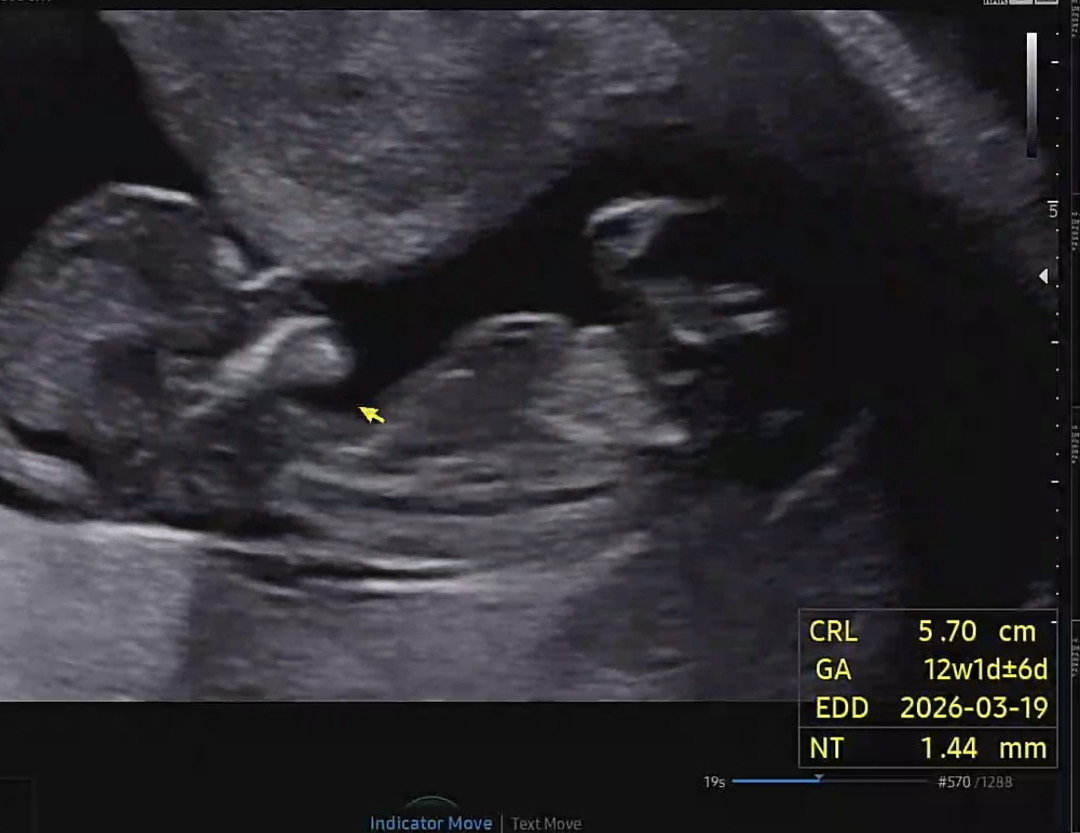

12주 1일각도법 고수님들 도와주세요

첫째가 아들이라 남편이 둘째는 딸을 엄청 원해서요!! 저는 각도법 아무리 봐도 잘모르겠어서 각도법 고수님들 딸인지 아들인지 한번 봐주세요🙏🏻